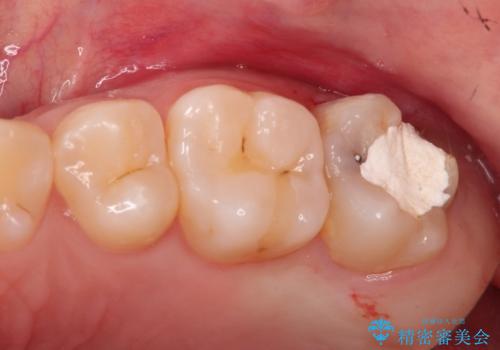

- 前歯の変色を主訴に来院されました。

歯茎のラインも整っていなかったため、手術を行いきれいな被せ物をいれることができました。

歯茎のラインを整える手術を行ったあとは、しばらく待ってから被せ物の治療を行っていきます。